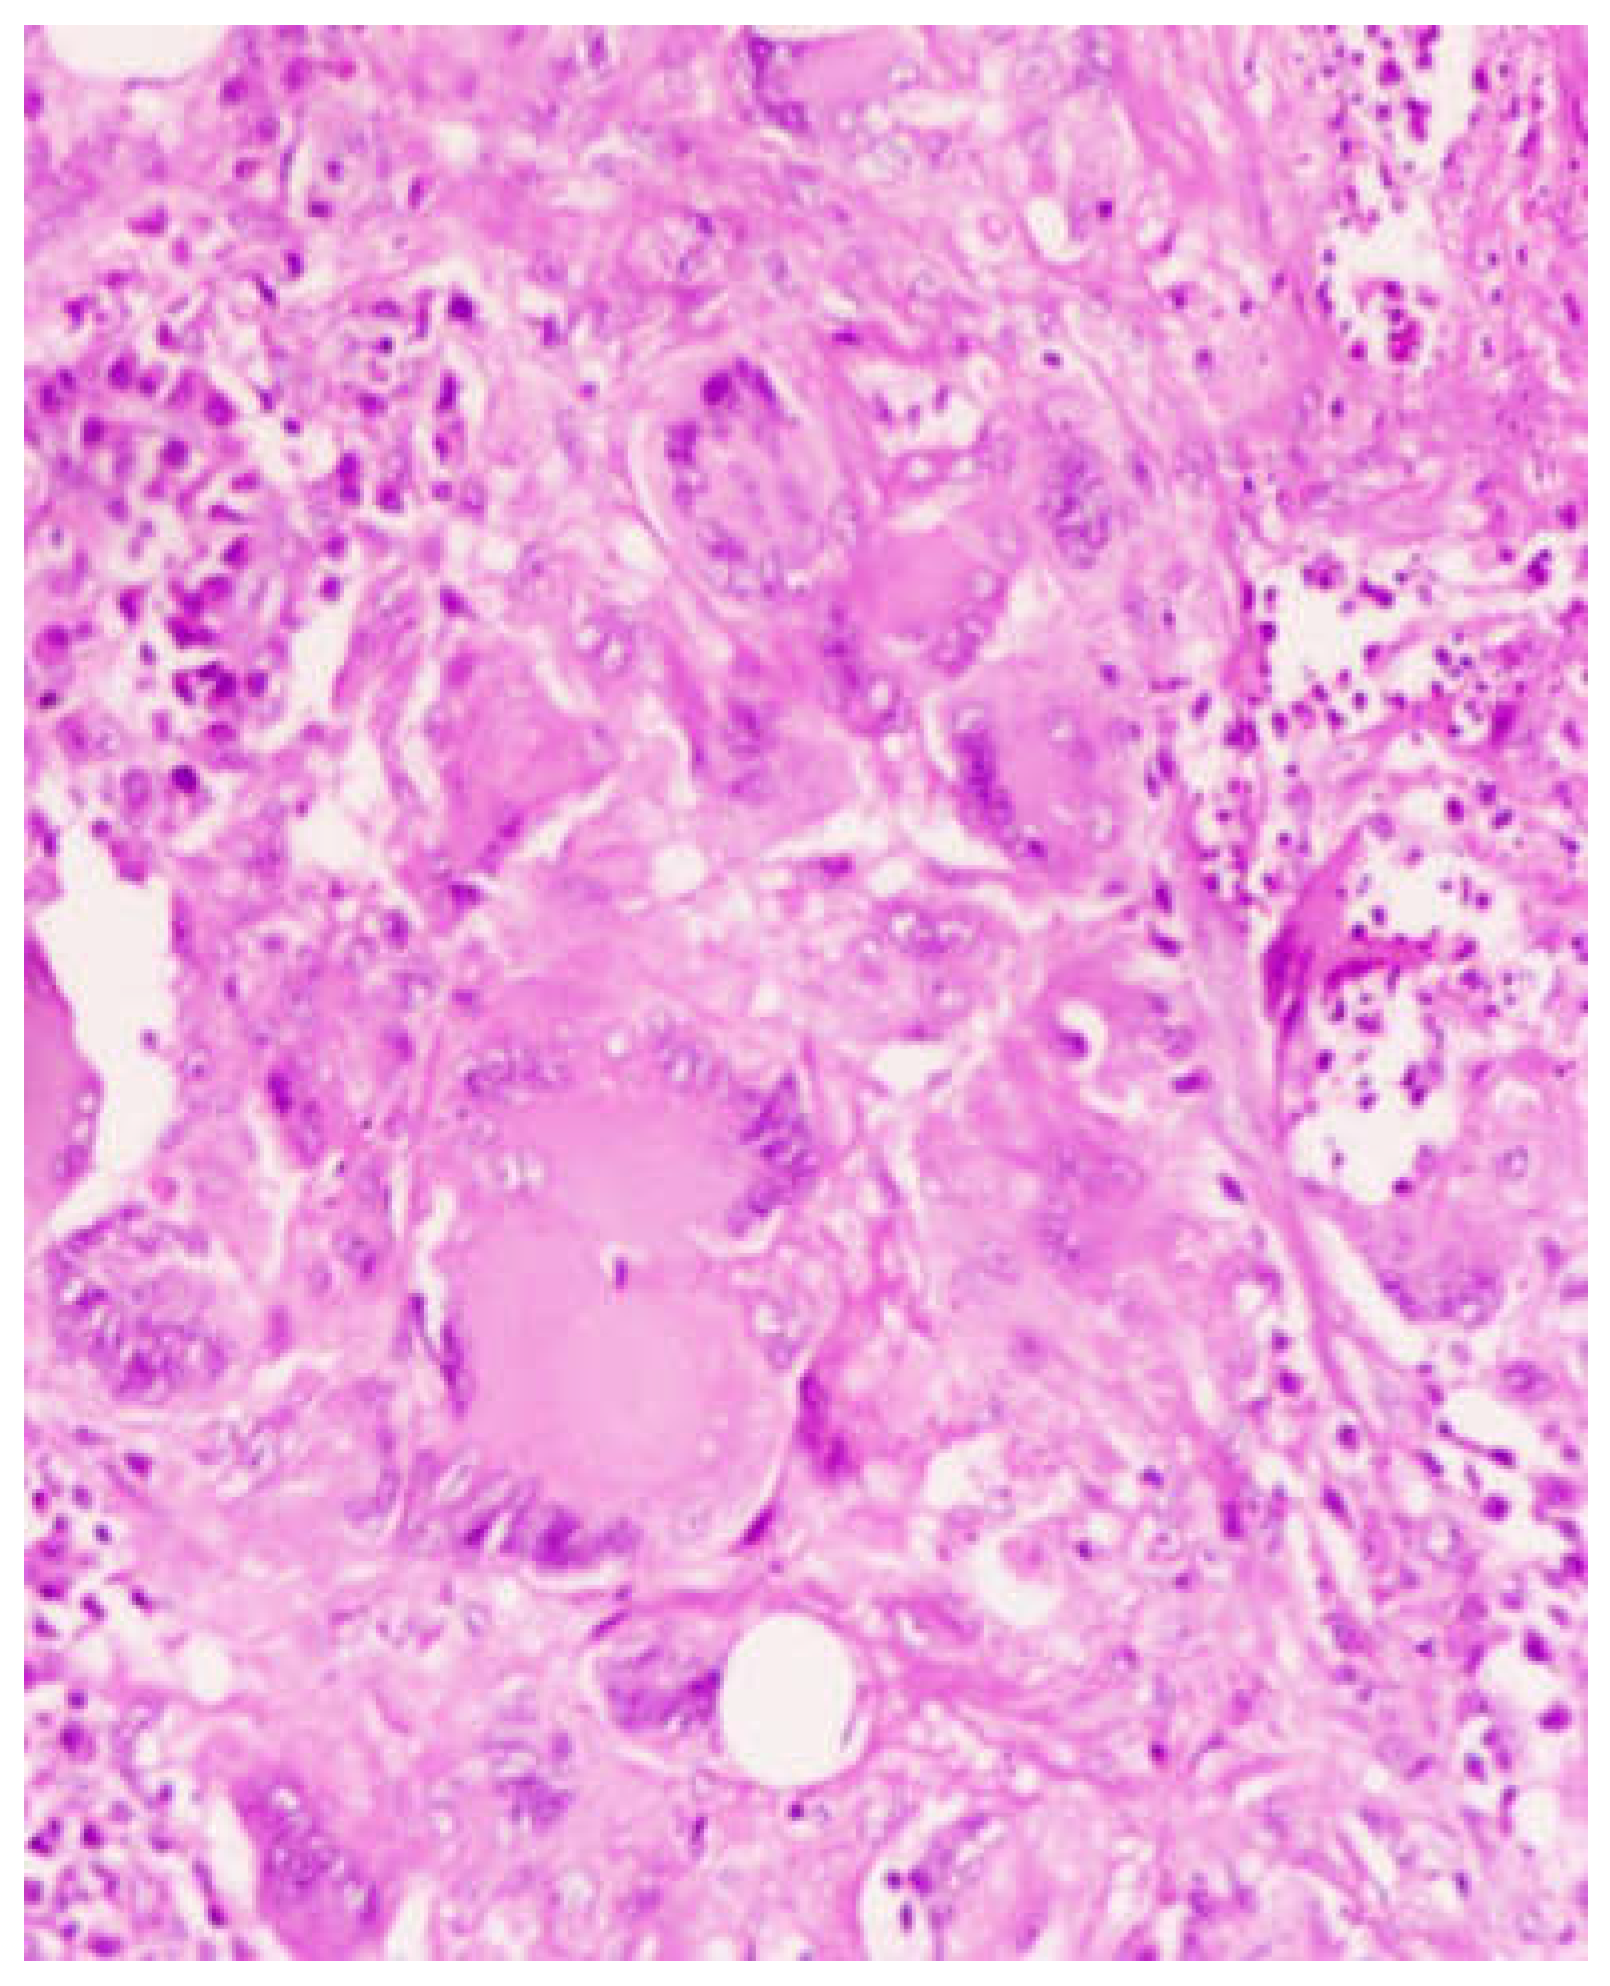

The patient was counseled regarding the possible nature of the condition and also regarding the need of undergoing surgical procedure to reach a proper diagnosis. The case was presented in the institutional tumor board meeting and a consensus was reached regarding the treatment plan. An open medial maxillectomy was performed with complete removal of the tumor (Figure 2). The histopathological examination showed numerous multinucleated giant cells in the background of chronic inflammation with signs of non caseating granulomatous changes (Figure 3). On Grocott’s Methanamine Silver staining (GMS staining) dark brown colored septate fungal hyphae was seen (Figure 4). On fungal culture with malt extract agar as culture media, the presence of aspergillus flavus was confirmed. Cartridge based nucleic acid amplification tests for mycobacteria species showed a negative result. With the histopathological and microbiological evidences a diagnosis of CGIFS was made and the patient was put on voriconazole 200mg twice daily for 12 weeks under liver function monitoring fort nightly. Patient showed no signs of recurrence till three months of follow up.

Figure 3. Tissue specimen with Hematoxylin and Eosin staining (100x magnification) showing non caseating granuloma formation in the back ground of chronic inflammatory changes (Presence of multinucleated giant cells can be seen).